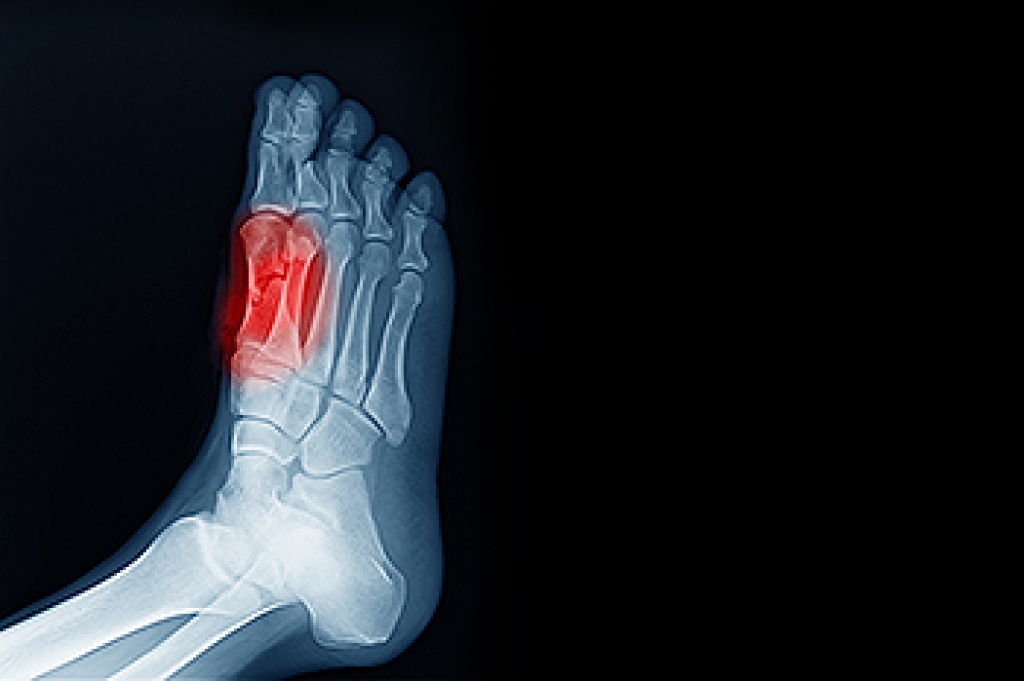

Ankle impingement occurs when soft tissues, such as ligaments or tendons, become pinched between the bones of the ankle joint, leading to pain and restricted movement. This condition often develops due to repetitive ankle use or trauma, such as a sprain, making it common among athletes, dancers, and individuals with occupations requiring repetitive ankle motion. People with ankle impingement typically feel a sharp, localized pain at the front or back of the ankle. The pain may worsen with certain movements, like deep squats, running, or jumping. Stiffness, swelling, and a clicking sensation might also accompany the discomfort. Diagnosing ankle impingement involves a physical exam, patient history, and imaging like X-rays or MRI scans to identify structural changes. Treatment ranges from rest and targeted exercises to cortisone injections or, in severe cases, surgery to relieve the pressure and restore mobility. If you have ankle pain, it is suggested that you schedule an appointment with a podiatrist for a proper diagnosis and treatment.

Due to the wide variety of potential causes of ankle pain, podiatrists will utilize a number of different methods to properly diagnose ankle pain. This can include asking for personal and family medical histories and of any recent injuries. Further diagnosis may include sensation tests, a physical examination, and potentially x-rays or other imaging tests.